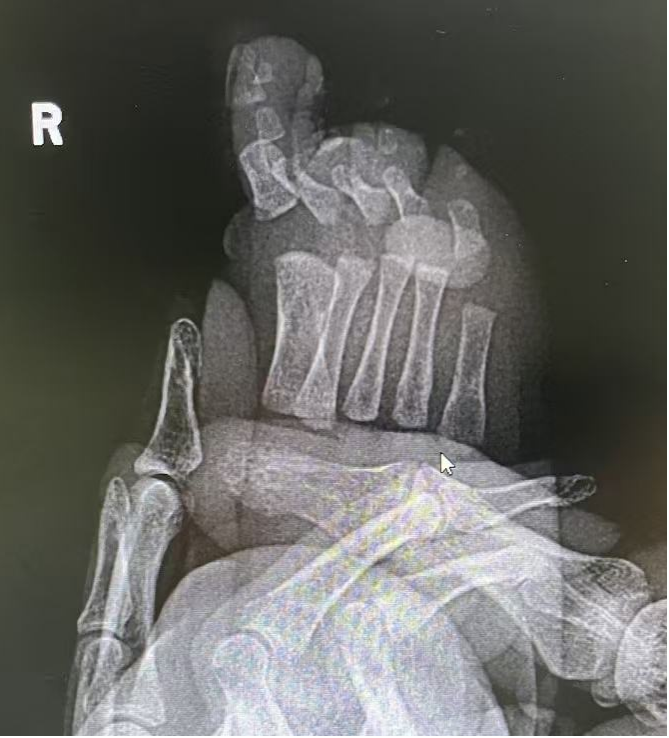

就诊时照片:

精准诊断:明晰畸形,制定个性化方案

经过细致的体格检查和 X线检查,医生明确诊断患儿为双手、双足均多指(趾)畸形。影像结果显示,左足多出的第 6趾内部存在骨性结构,与正常的跖骨相关联,这增加了手术的复杂性,并非简单的软组织切除。